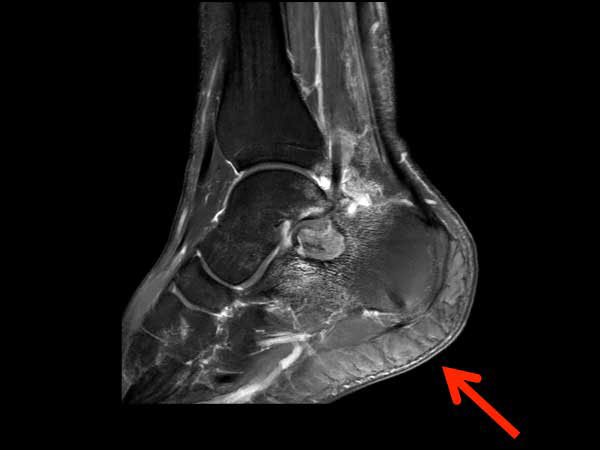

Sagittal T2w mDIXON